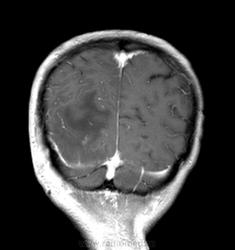

Мужчина проходит курс химиотерапии по поводу Т-клеточной лимфомы с первичным поражением кишечника (гистологическая верификация). За последний месяц - появление множественных очагов в печени, а также необычных изменений в голове.

- бесформенное образование в мягких тканях затылочной области, накапливающее контраст;

- утолщение твердой мозговой оболочки в той же области с накоплением контраста по пахименингиальному типу;

- отек прилежащей мозговой ткани с геморрагическими изменениями в коре, сопровождающийся масс-эффектом.

Мое мнение это лимфома кожи с прорастанием (если так можно сказать) через перфорирующие сосуды в ТМО, с кровоизлияниями в коре за счет повреждения сосудов. Либо это лептоменингальнаые проявления лимфомы. Больше на ум ние чего не приходит. Хотелось бы услышать мнение более опытных специалистов. но все почему-то молчат...

Я тоже думаю, что это лимфома. Думаю, не так важно, прорастает ли она из мягких тканей в мозговые оболочки, или наоборот. Только поражение мозговой оболочки - это пахи-, а не лептоменингиальные изменения.

В таком случае изменения в мозговой ткани - это отек, обусловленный нарушением венозного оттока по поверхностным венам; думаю, вкупе с геморрагическими изменениями этот отек можно квалифицировать как венозный инфаркт.